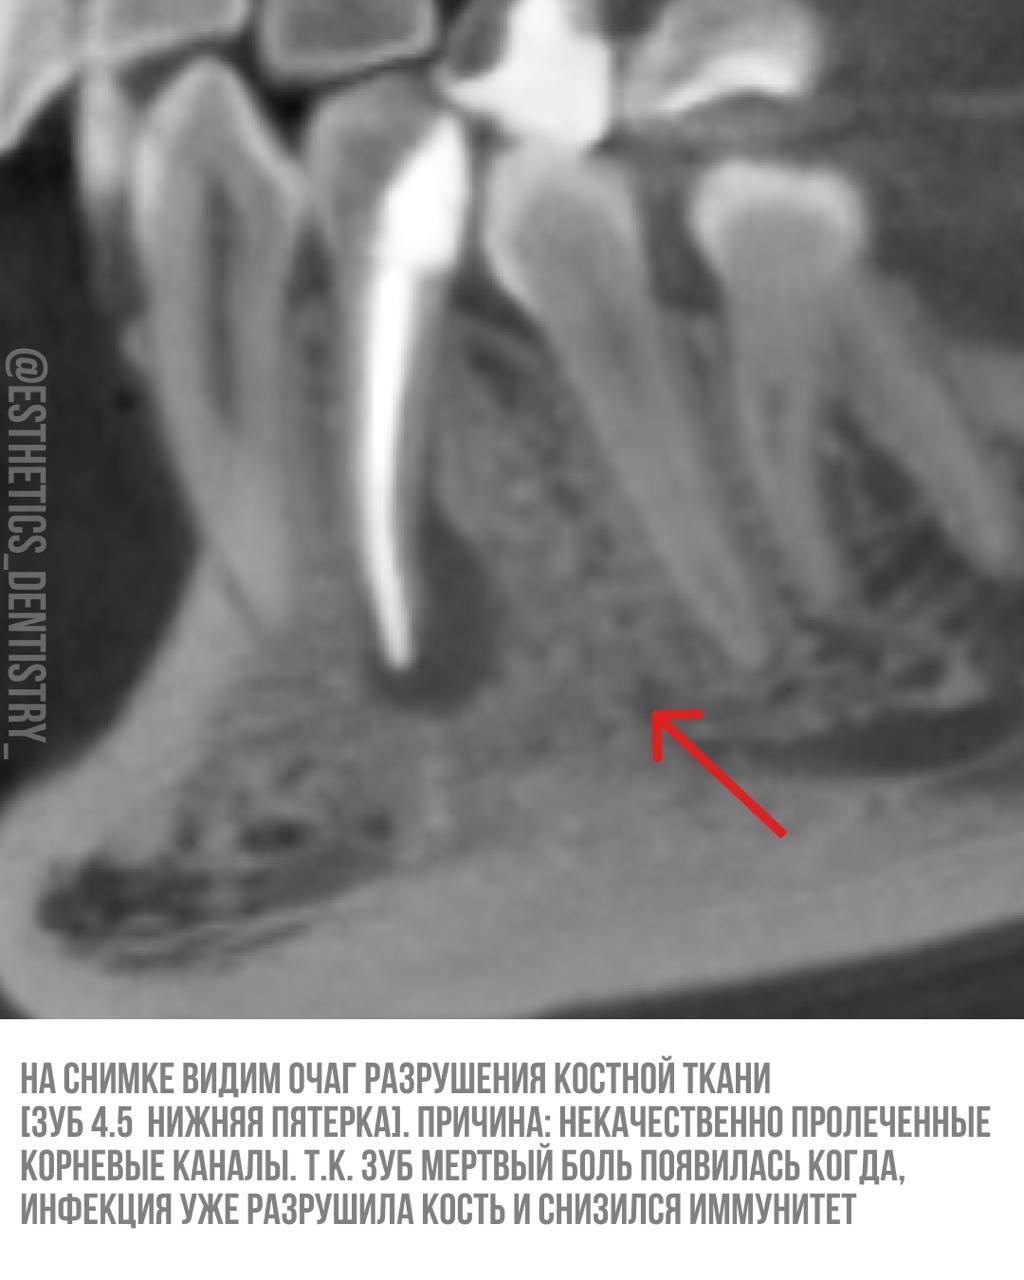

Кейс лечение кисты

Терапия